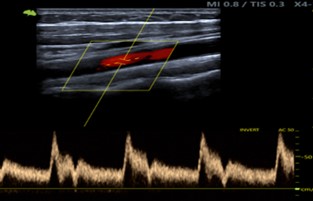

En las Imágenes A y B se valoran las arterias del eje carotídeo, presentando carótida común, externa e interna: flujos anterógrados laminares conservados con velocimetría conservada.